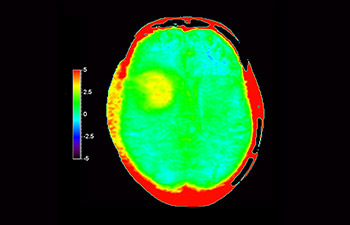

Numa sociedade para a qual os distúrbios neurológicos representam um fardo pesado, a Philips está empenhada em proporcionar uma extraordinária clareza de diagnóstico e orientações de tratamentos para todos os pacientes. Atualmente, embora a RM seja o padrão de excelência no diagnóstico por imagem em neuro-oncologia, sua precisão na classificação de tumores e na avaliação de acompanhamento dos tratamentos pode ser aprimorada. O APT (Amide Proton Transfer) 3D é um método exclusivo de diagnóstico por imagem por RM do cérebro sem contraste que aborda a necessidade de um diagnóstico mais confiante em neuro-oncologia. O APT 3D utiliza a presença de proteínas celulares endógenas para produzir um sinal de RM que se correlaciona diretamente com a proliferação celular, um marcador de atividade tumoral. O APT 3D pode auxiliar profissionais de saúde capacitados na diferenciação entre gliomas de baixo e de alto grau e a diferenciar a progressão tumoral do efeito do tratamento.1

com o APT 3D